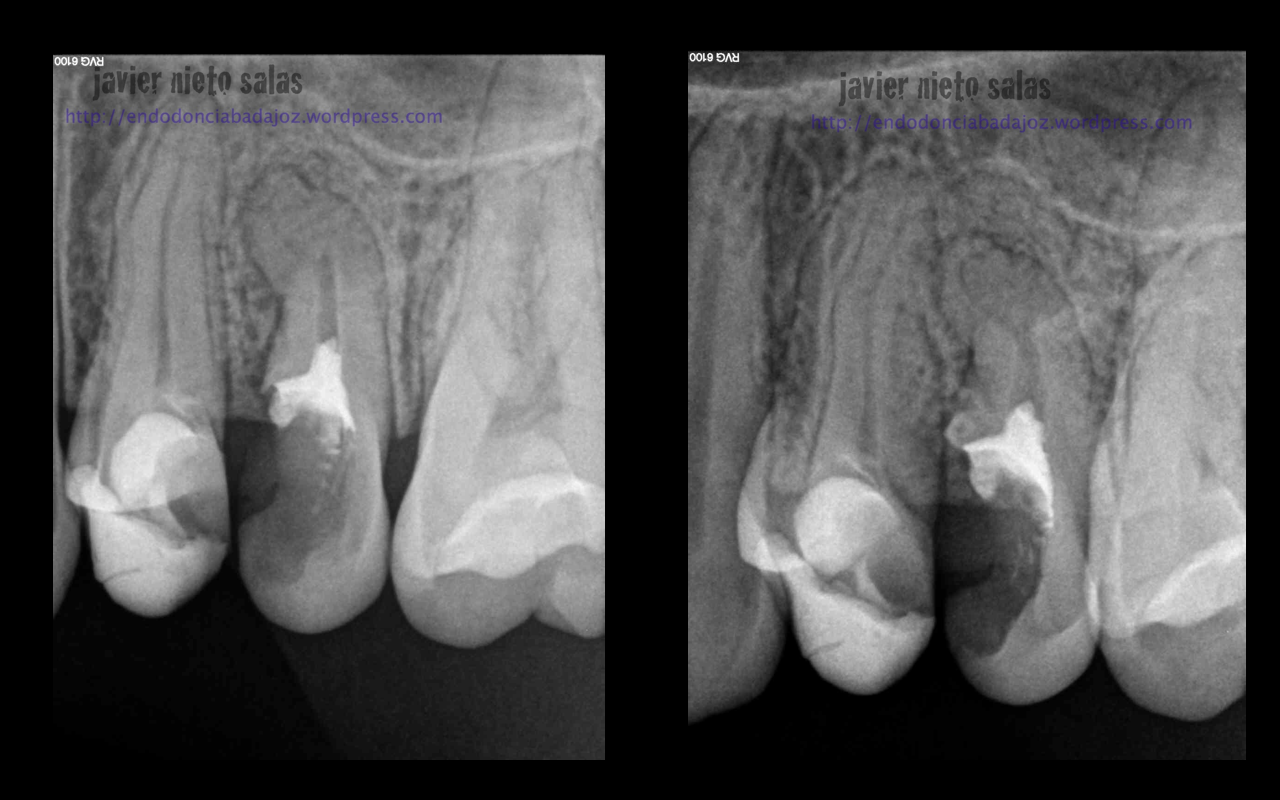

Hay casos más o menos complicados, que debemos plantearnos como afrontarlos, y en ocasiones nos sorprenden con esos conductos laterales que obturamos por la buena limpieza y obturación que empleamos.

O por el contraio este otro, que he de decir que me costó muchísimo, pero que gracias a poder estudiar el caso y a la ayuda de la magnificiación pudimos tratarlo correctamente: